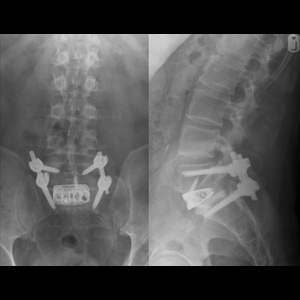

Spinal stenosis (Lumbar) Spinal stenosis (Cervical) Spinal stenosis (Thoracic) Lumbar Disc Herniation Spondylolisthesis Cervical Foraminal Stenosis Vertebroplasty Lumbar Fusion Anterior Cervical Fusion (ACDF) Posterior Cervical Fusion Thoracic Fusion Revision Lumbar Fusion Surgery Facet Joint Cyst Spinal Tumour Minimally Invasive Lumbar Fusion (XLIF) Minimally Invasive Lumbar Fusion (ALIF) Lumbar Fusion (TLIF) Thoraco-lumbar Fusion Lumbar Corpectomy Complex Lumbar Spine Surgery (Spino-pelvic fixation) Complex Cervical Spine Surgery Complex Thoracic Spine Surgery Occipito-cervical Fusion Minimally invasive surgery for thoracic disc herniation Other Related Topics